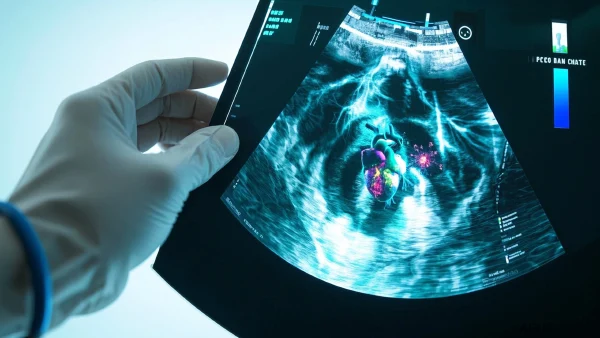

03. 超声心动图:病毒性心肌炎的“眼睛”

说到确诊病毒性心肌炎,超声心动图(彩超)是临床最常用也是最实用的工具。它类似于给心脏实时做个“体检”,能看到心脏结构和运动情况,还能帮医生判断心肌损害的位置和程度。和抽血、心电图等比起来,超声心动图有几点特别的优势:

04. 超声检测:病毒性心肌炎常见的异常表现

其实,很少有其他疾病能像心肌炎一样,让心脏的结构和功能短时间内出现多种变化。通过超声心动图,临床医生会特别关注这些关键标志:

- 心肌增厚或变薄:心肌区域肿胀,显示厚度异常波动

- 心脏收缩变弱:心脏泵血时的“劲头”不足,射血分数(EF值)下降

- 心腔扩大:心腔体积明显增大,常常提示炎症严重

- 心脏局部运动异常:某片心肌“动不了”、运动相反

- 心包积液:炎症导致心脏“周围加水”(心包液增多)